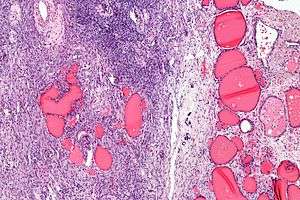

Micrograph of a struma ovarii. Characteristic thyroid follicles are seen on the right, and ovarian stroma on the left. H&E stain.

A struma ovarii (literally: goitre of the ovary) is a rare form of monodermal teratoma that contains mostly thyroid tissue, which may cause hyperthyroidism.[1]